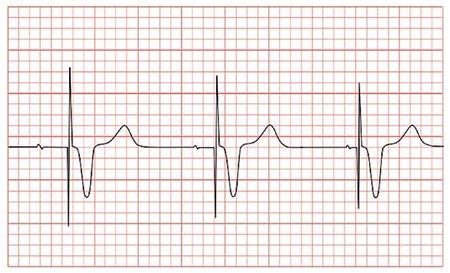

Důsledky EMI vyvolané monopolárním elektrochirurgickým zařízením jsou nepředvídatelné a mohou se projevit jako inhibice kardiostimulace (chybějící impuls), spuštění asynchronní kardiostimulace, přeprogramování softwaru, resetování přístroje a poškození obvodů kardiostimulátoru (MHRA, 2006). Armstrong a Williams (2007) tvrdí, že při použití monopolárních elektrochirurgických nástrojů může silný radiofrekvenční proud procházet přímo do srdce pacienta s implantovaným kardiostimulátorem. To může narušit správnou funkci kardiostimulátoru, protože tento proud může poškodit citlivé tkáně a snížit jejich citlivost k signálům kardiostimulátoru. Protože je pacient na operačním stole a není při vědomí, není schopen se vzdálit od zdroje interference nebo informovat o jejích důsledcích. O tom, zda je vhodné použít monopolární elektrochirurgické zařízení s určitými pohotovostními opatřeními, nebo alternativní metodu hemostázy, rozhodují anesteziolog a chirurg na základě rad z kardiologické kliniky, kde je pacient sledován.

MHRA (2006) dále radí, aby při po užití monopolárních elektrochirurgických zařízení byl pacient pečlivě sledován anesteziologem, který je schopen interpretovat informace z EKG, a pomocí pulsního oximetru jako alternativní metody, nebo detekce pulsu pacienta. Doporučuje, aby všechny kabely připojené na elektrochirurgické zařízení byly vedeny co nejdál od místa implantace kardiostimulátoru a aby disperzní elektroda byla umístěna tak, aby elektrický proud mezi aktivní a tou to disperzní elektrodou procházel co nejdál od elektrod kardiostimulátoru i samotného kardiostimulátoru. Při výskytu jakýchkoliv známek inhibice funkce kardiostimulátoru musí anesteziolog okamžitě informovat chirurga, aby mohla být aplikace přerušena nebo ukončena.